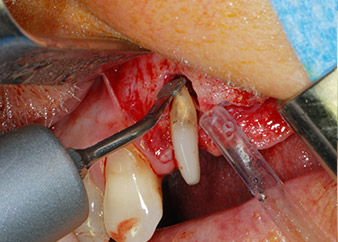

Vor der Insertion der Implantate wurde infiziertes Weichgewebe im Implantationsbereich und um das Abutment mit einem Instrument entfernt, das laut Hersteller primär zur Knochenbearbeitung und zum Sammeln von Knochenspänen vorgesehen ist (Piezomed, Einsatz B5) (Abb. 6 und 7).